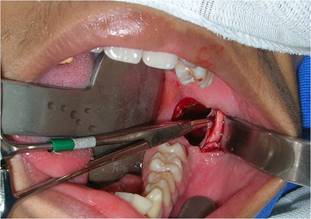

En secuencia, se realizó una incisión circunferencial con un mango para bisturí n.º 3 equipado con una lámina 15, lo suficientemente profunda para penetrar al interior de la lesión. Además de extraer este tejido, también se extrajo un fragmento de la cápsula de la lesión por separado, con el fin de obtener una muestra más específica de la lesión (Fig. 4).